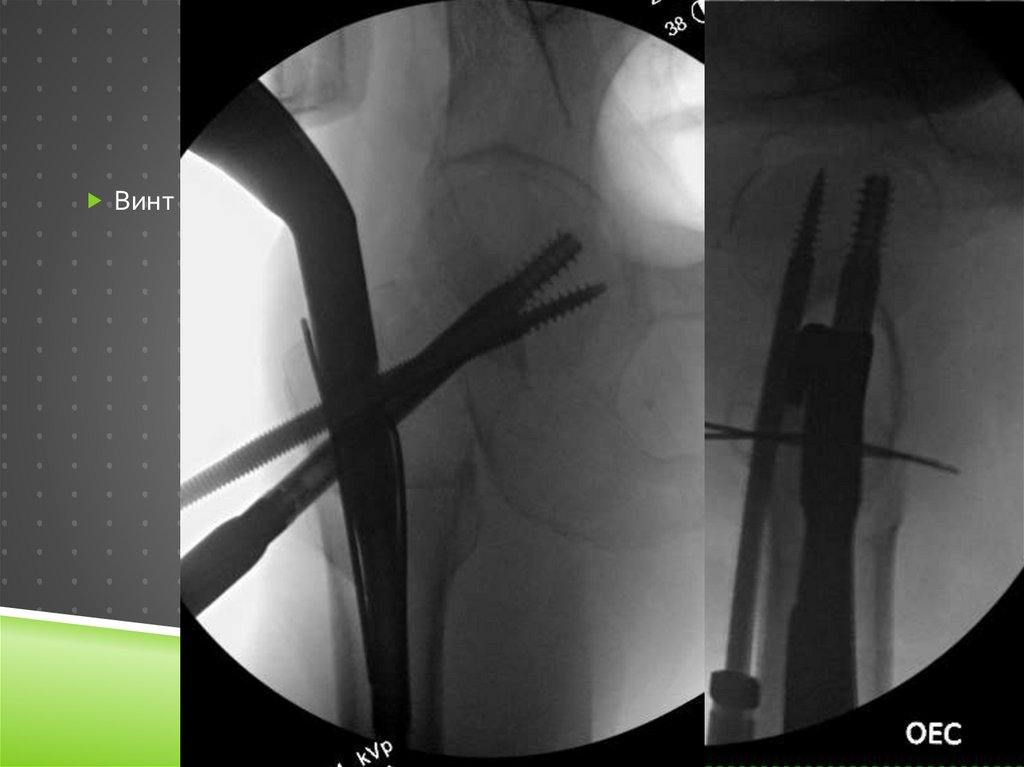

Intra-op